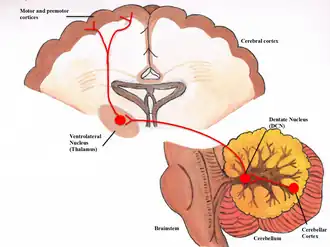

The cerebello-dentato-thalamo-cortical pathway. The figure depicts the pathway from the cerebellum to the motor cortex, via the ventrolateral nucleus of the thalamus. | |

The dentatothalamic tract (or dentatorubrothalamic tract) is a tract which originates in the dentate nucleus, follows the ipsilateral superior cerebellar peduncle, decussates later on reaching the contralateral red nucleus and the contralateral thalamus.[1]

The term "dentatorubrothalamocortical" is sometimes used to emphasize termination in the cerebral cortex.[2]